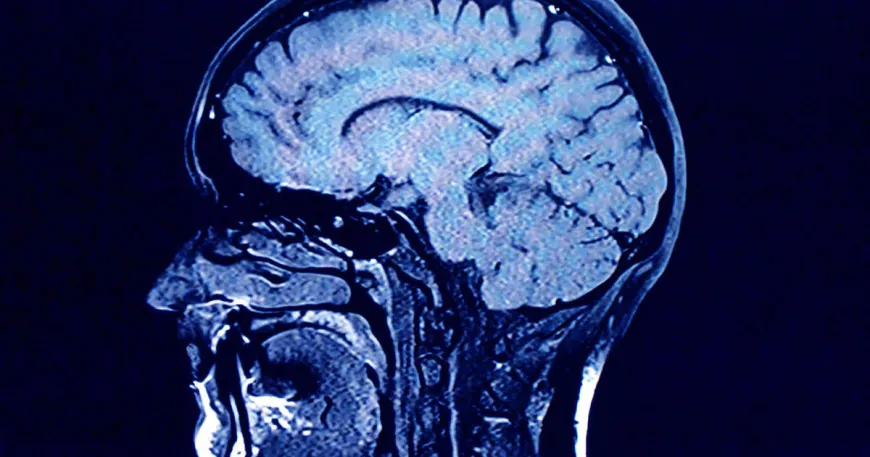

Human brains contain higher concentrations of microplastics than other organs, according to a new study, and the amount appears to be increasing over time.